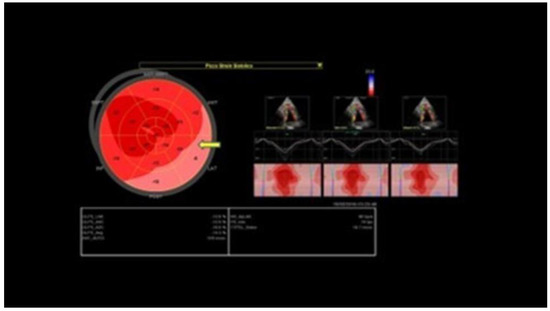

Chronic or Changeable Infarct Size after Spontaneous Coronary Artery Dissection

by Gordana Krljanac, Svetlana Apostolovic, Zlatko Mehmedbegovic, Olga Nedeljkovic-Arsenovic, Ruzica Maksimovic, Ivan Ilic, Aleksandra Djokovic, Lidija Savic, Ratko Lasica and Milika Asanin

Diagnostics 2023, 13(9), 1518; https://doi.org/10.3390/diagnostics13091518 - 23 Apr 2023

Spontaneous coronary artery dissection (SCAD) could be the cause of acute myocardial infarction (AMI) and sudden cardiac death. Clinical presentations can vary considerably, but the most common is the elevation of cardiac biomarkers associated with chest discomfort. Different pathological etiology in comparison with [...] Read more.

Spontaneous coronary artery dissection (SCAD) could be the cause of acute myocardial infarction (AMI) and sudden cardiac death. Clinical presentations can vary considerably, but the most common is the elevation of cardiac biomarkers associated with chest discomfort. Different pathological etiology in comparison with Type 1 AMI is the underlying infarct size in this population. A 42-year-old previously healthy woman presented with SCAD. Detailed diagnostical processing and treatment which were performed could not prevent myocardial injury. The catheterization laboratory was the initial place for the establishment of a diagnosis and proper management. The management process can be very fast and sometimes additional imaging methods are necessary. Finding predictors of SCAD recurrence is challenging, as well as predictors of the resulting infarct scar size. Patients with recurrent clinical symptoms of chest pain, ST elevation, and complication represent a special group of interest. Therapeutic approaches for SCAD range from the ”watch and wait” method to complete revascularization with the implantation of one or more stents or aortocoronary bypass grafting. The infarct size could be balanced through the correct therapeutical approach, and, proper multimodality imaging would be helpful in the assessment of infarct size. Full article